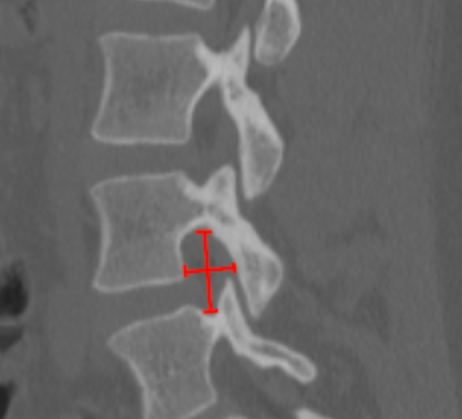

Pars Interarticularis Defects